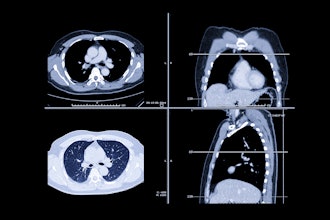

Adherence to LCS decreases after baseline screening